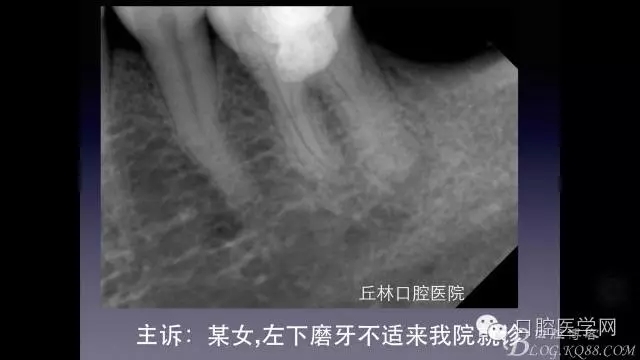

一例36根管再治療,五個根管冷側(cè)加壓病例